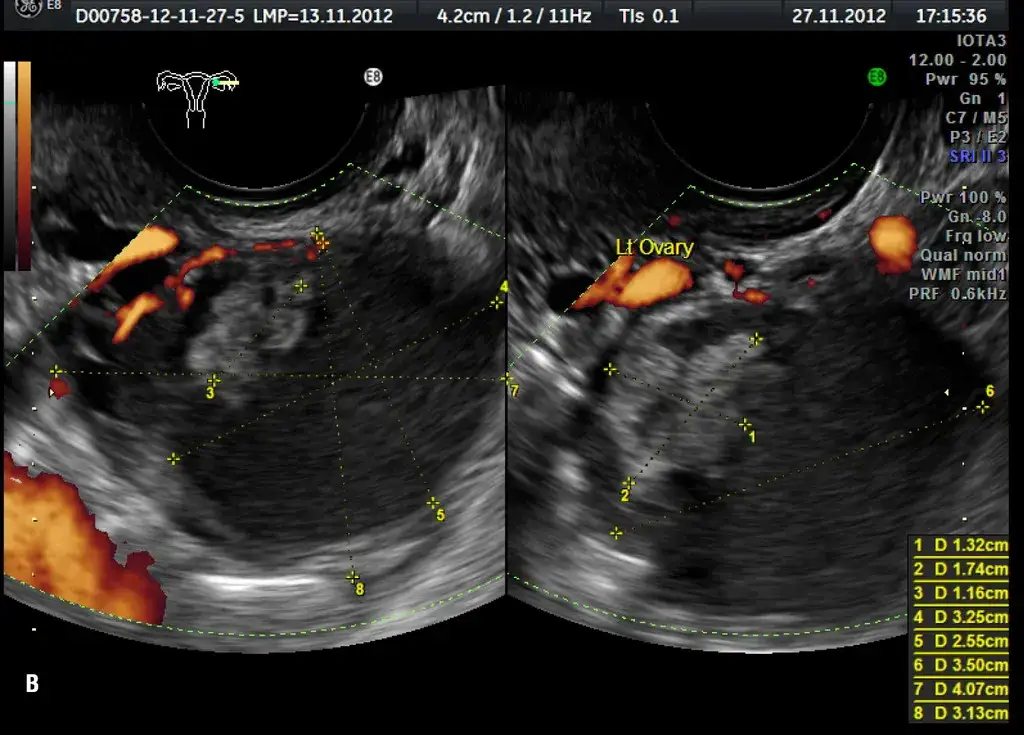

Torbiele na jajnikach: czy zawsze są groźne i jakie dają objawy?

Torbiele jajników to dość częsta dolegliwość, która może być przyczyną bólu w podbrzuszu. Większość z nich toZapalenie przydatków (PID): jak rozpoznać ostrą infekcję wymagającą leczenia?